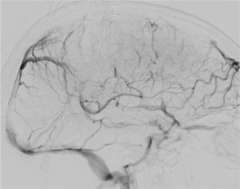

Figure 2

The blockage can result in brain swelling (edema), stroke, and/or bleeding in the brain (Figure 2).